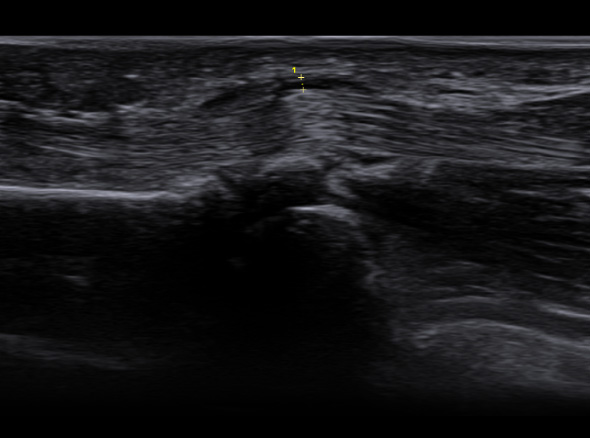

학술적으로는 협착성 굴곡건염이라고 표현하고, A1 활차라는 터널에 굽히는 힘줄이 마찰되다가 힘줄의 내부적인

변화가 일어나 병이 생긴 상태를 의미합니다. 내부적인 변화가 심해질 경우 힘줄이 부어 결절을 이룰 수도 있는데

이러한 경우 A1 활차에 끼어서 딸깍 거리거나 걸려서 안 펴지는 증상이 생깁니다.